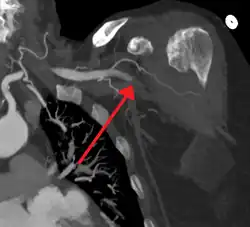

| Acute embolism to the right femoral artery resulting in ischemia | |